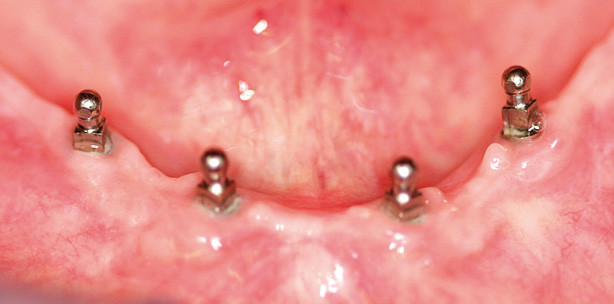

Eine 82-jährige Nichtraucherin mit einem guten allgemeinen Gesundheitszustand klagte über regelmäßige Druckstellen und unzureichenden Halt ihrer Unterkieferprothese während des Kauens. Zwei Versuche, Implantate mit konventionellem Durchmesser zu inserieren, waren bereits fehlgeschlagen. Deshalb wurde entschieden, vier 3M™ ESPE™ Mini-Dental-Implantate einzu­setzen. Zunächst wurde eine Röntgenaufnahme angefertigt, um die Platz­verhältnisse zu analysieren (Abb. 1). Auf Basis dieser Daten wur-den einteilige Implantate mit einem Durchmesser von 1,8mm und 15mm Länge sowie einem Kugelkopf für die Verankerung der Prothese ausgewählt. Anschließend wurden mit 1,1-mm-­Bohrern Pilotbohrungen vorgenommen. Dieser Bohrerdurchmesser ist ­ausreichend, da die Implantate ein selbstschneidendes Design aufweisen. Die Kondensation und Kompression des Knochens, die bei der Insertion entsteht, ist wichtig für die Primärstabilität der Implantate. Mit den Bohrern wurde anschließend die parallele Position der Bohrlöcher überprüft (Abb. 2). Es folgte die Insertion der Mini-Implantate und eine Abformung mit der bestehenden Prothese, um die Implantatpositionen auf deren Basis zu markieren (Abb. 3 und 4). Daraufhin wurde erneut eine Röntgenaufnahme angefertigt, um die Impantatpositionen zu überprüfen. Die Matrizen wurden zudem in die Prothesenbasis einpolymerisiert. Die Implantate wurden sofort belastet. Dies war dank einer ausreichenden Primärstabilität sowie der Tatsache möglich, dass die Prothese auch vom Weichgewebe getragen wird. In regelmäßigen Kontrolluntersuchungen wurden gesunde Weichgewebeverhältnisse festgestellt (Abb. 5). Auf der Röntgenaufnahme nach zwölf Monaten zeigte sich keinerlei periimplantärer Knochenabbau (Abb. 6a und b).